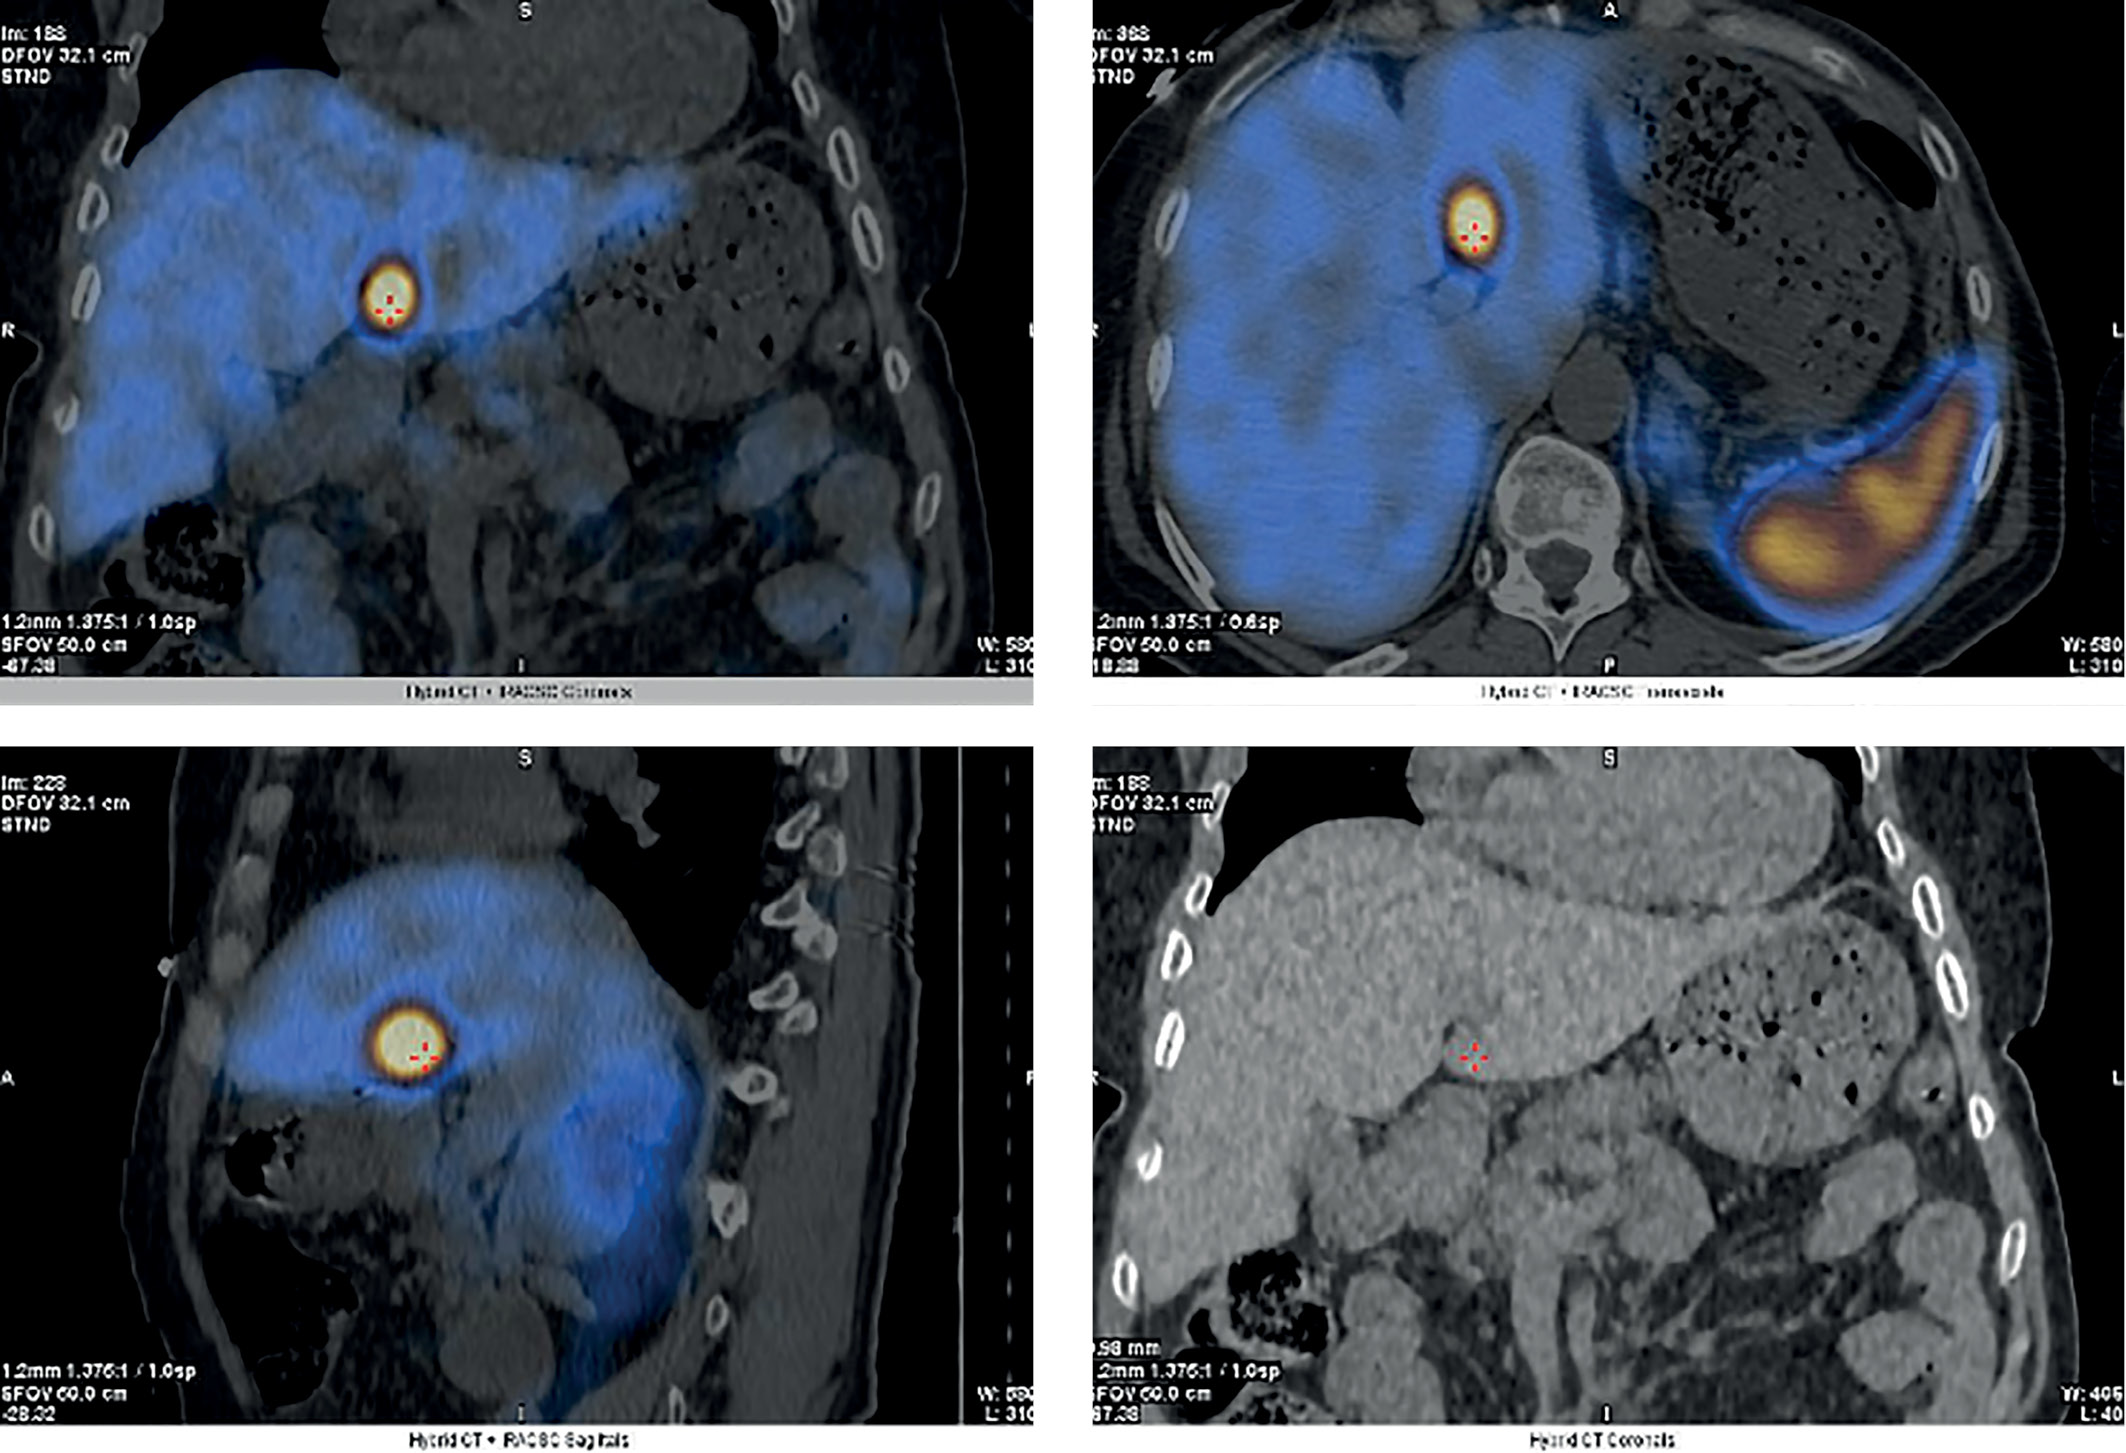

5. Рисунок 5. Сцинтиграфия с Тс99m–Тектротидом с ОФЭКТ/КТ. Красными метками отмечен очаг в SIV печени с гиперэкспрессией соматостатиновых рецепторов. | |